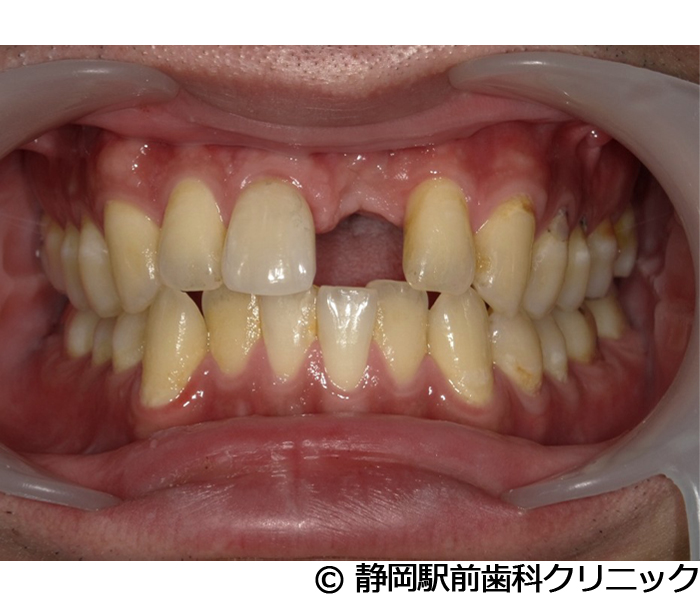

【症例2】上顎前歯単独インプラント埋入

- 治療前

- 治療後

- 治療名

- 上顎前歯単独インプラント埋入

- 費用

- 385,000円(税込)

- 期間

- 7ヵ月

治療内容

-

患者様の症状

上の前歯の入れ歯を使っていたが、違和感があるし、毎日手入れが大変なのでインプラント治療希望。

治療方法

術前にCTや歯型などの資料を取り、前歯のため審美性も考慮し、綿密に治療計画を立てました。その後、インプラントを埋入し、人工歯を被せて審美と咬合の回復を行いました。

治療結果

自分の歯のような見た目で、違和感もなく噛むことができてご満足いただくことができました。

※治療結果は個人差があります。

治療を行う上での注意点(リスク・副作用)

術後は、出血、腫れ、痛みなどが出る可能性があります。